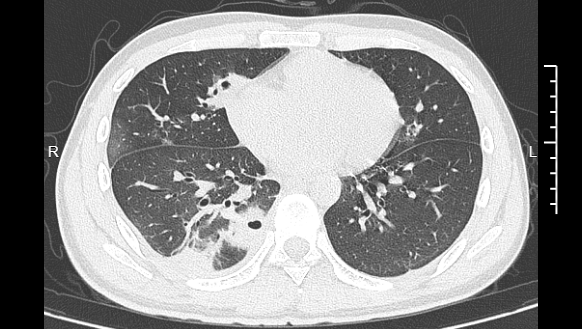

熬到第三天,小林已经烧到39℃,赶紧来到宁波大学附属第一医院就诊。接诊的丁群力主任医师一看他的症状,立刻安排了CT检查。结果显示:小林的肺里有十几个空洞,部分肺组织已经坏死,这是典型的血源性肺脓肿。

小林的CT影像显示肺里有多个空洞